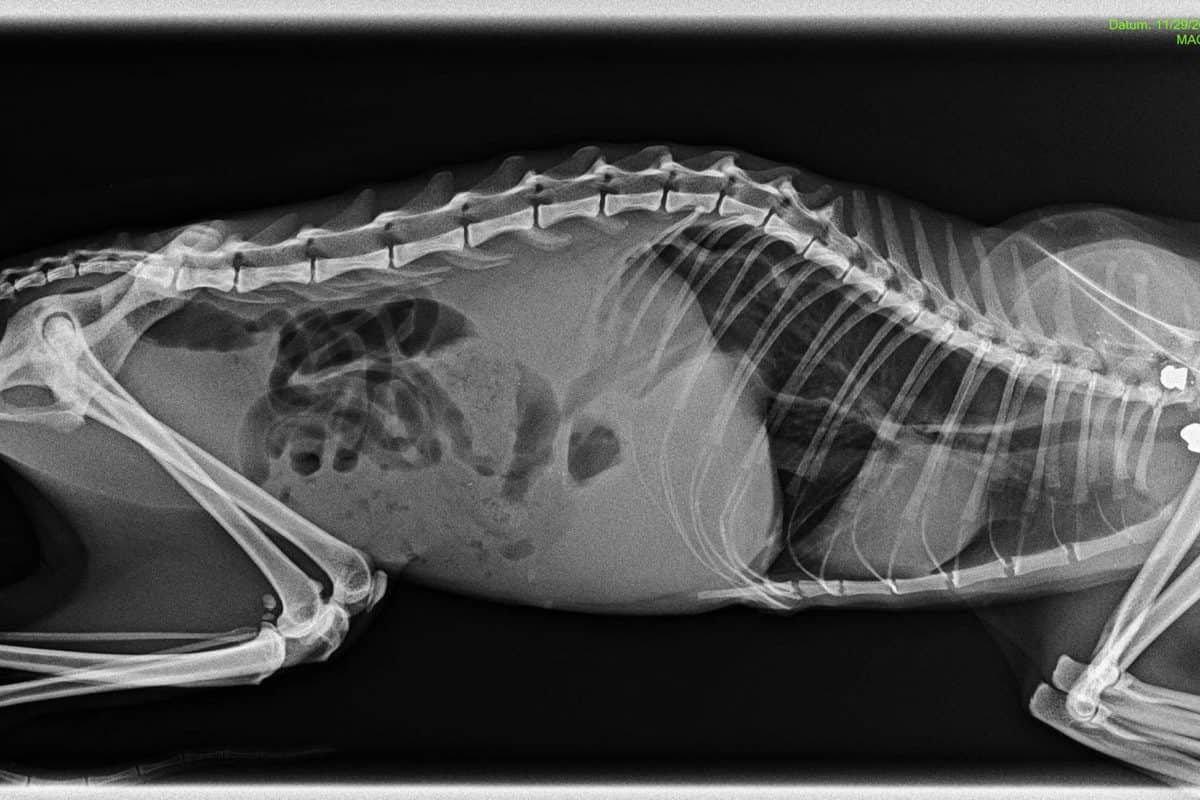

Kot je Maja zapisal na svojem profilu, je neznani storilec 30. novembra njeno mucko Frido na območju Šmiklavža najprej dvakrat ustrelil, a na srečo zgrešil vse vitalne organe. Ker pa očitno to ni bilo dovolj, je žival najverjetneje še udaril z lopato ali drugim topim predmetom, saj ima mucka Frida zdrobljen kolk.

Na srečo je mucki kljub hudim poškodbam uspelo priti do doma, kjer je pred pragom počakala na lastnico Majo, ki jo je nemudoma odpeljala na veterinarsko postajo. Tam so jo oskrbeli, vendar pa se Frida še vedno bori za življenje.